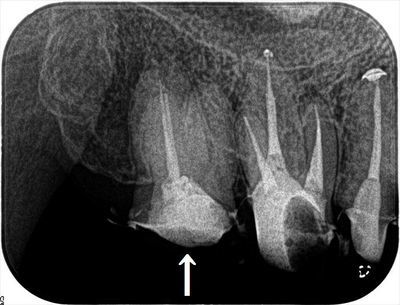

治療前のデンタルX線写真です。

矢印を付けた右上第二大臼歯の再根管治療を行います。

手つかずであった近心頬側根管を含め前回の治療までに3根管とも根尖まで無事に攻略できました。

本日、症状ないことからサーマフィルによる垂直加圧根管充填を行いました。